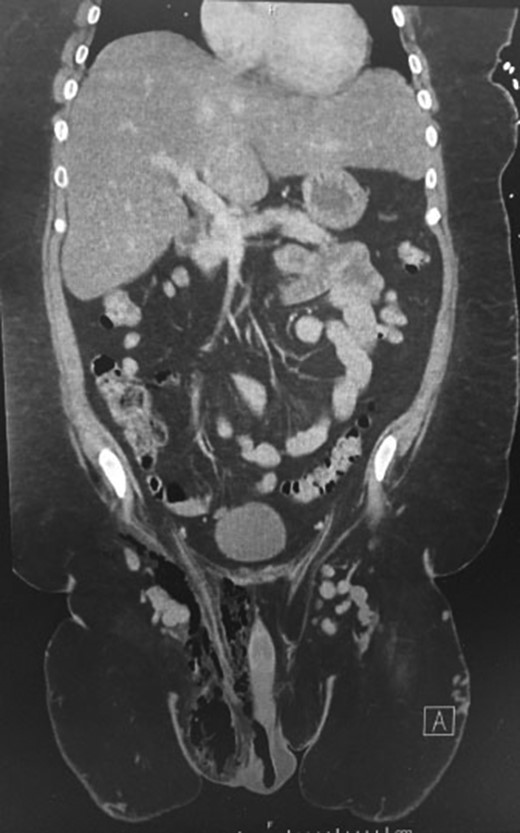

A 45-year-old male, with a background of type 2 diabetes mellitus and morbid obesity (BMI 40.9) presented septic to the Emergency Department, with a one-week history of increasing scrotal pain, penile discomfort, and difficulty ambulating. He was febrile and tachycardic on presentation. Physical examination revealed a grossly swollen and oedematous scrotum with tissue necrosis evident over the right posterior hemiscrotum. Erythema and induration extended to the rectum, pubic and right inguinal regions. Biochemistry revealed a polymorphonuclear leucocytosis, hyperglycaemia and lactic acidosis. A computed tomography scan of his abdomen/pelvis confirmed a markedly oedematous right hemiscrotum with extensive subcutaneous emphysema tracking into the right inguinal region and anterior abdominal wall (Figs 1 and 2).

Coronal CT scans of abdominopelvic region demonstrating gas and in the right groin region.